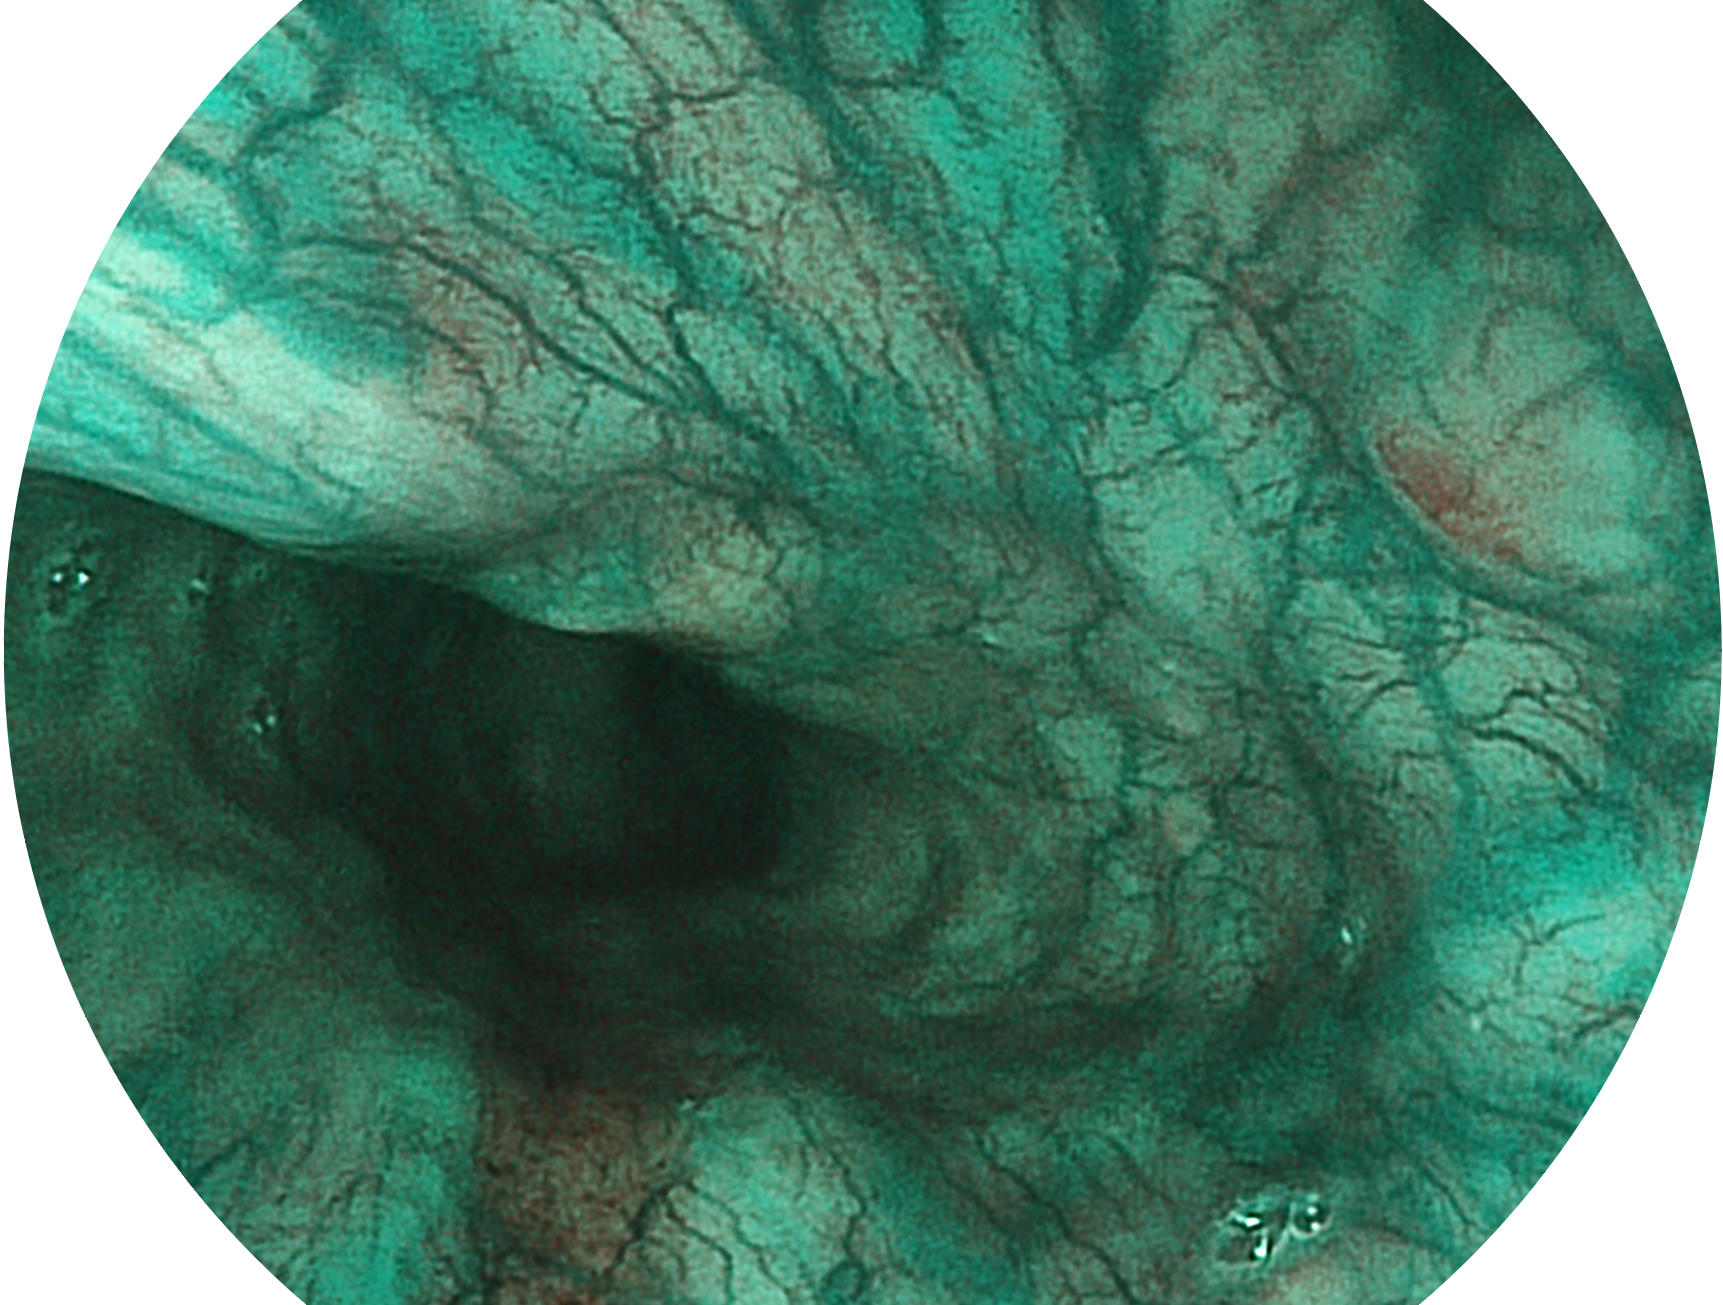

開立新開發(fā)的內(nèi)鏡染色技術(shù),主要是基于多波長(zhǎng)LED 光源的開發(fā),VLS-55Q 四波長(zhǎng)LED 光源是由四個(gè)不同顏色的LED光按照相應(yīng)照明模式所規(guī)定的特定發(fā)光比例進(jìn)行合束后形成,合束后形成的照明光的光譜由紅光、綠光、藍(lán)光及藍(lán)紫光這四個(gè)不同的波段范圍構(gòu)成。具有更高光譜自由度,通過光譜比例的控制,實(shí)現(xiàn)了聚譜成像技術(shù),英文全稱為“Spectral Focused Imaging, SFI”,縮寫為“SFI”和光電復(fù)合染色成像技術(shù),英文全稱為“Versatile Intelligent Staining Technology, VIST”,縮寫為“VIST”。